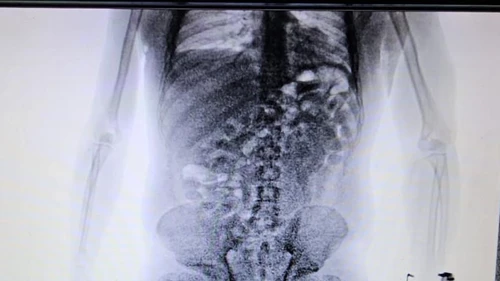

Durante la entrevista, el ciudadano de Brasil no logró explicar el motivo del viaje ni quién había comprado el pasaje aéreo. Además, dado el trayecto que realizaba, los agentes pensaron que podría estar ocultando drogas. Ante todos los indicios, los guardas inspeccionaron su equipaje pero no encontraron nada. Dado que las dudas persistían, decidieron utilizar otro método de control: el body scan

Las imágenes confirmaron las sospechas del personal aduanero dado que mostraban cuerpos extraños. Ante la posibilidad de que se tratase de un método de ocultamiento de estupefacientes, se internó al pasajero en un centro médico y lograron confirmar que había ingerido cápsulas con droga. En total eran 84 y contenían 1134 gramos de cocaína que en el país de destino se podría vender a USD 51 mil.